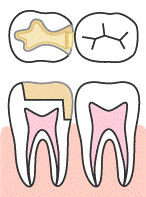

この段階の場合は歯髄付近まで達してはいますが、まだ歯髄は無事なので、C1と同様に虫歯になった部分を全て取り除き、詰め物を詰めるだけの処置で済みます。

ただし虫歯に侵されていて削った歯質が多い場合は、全体を覆うかぶせ物になる場合もあります。

虫歯を取り除いた後には、型取りをして、翌週にできた詰め物又はかぶせ物を付けられますので、2回で処置が終わります。

| 3.まもります | 神経を保護するために、セメントや薬剤でう窩を少し埋めます。 |

| 4.削ります | 詰め物の適合をよくするため、残った歯質の形を整えます。 |

| 5.型取り | 削った歯の型取りをします。 |